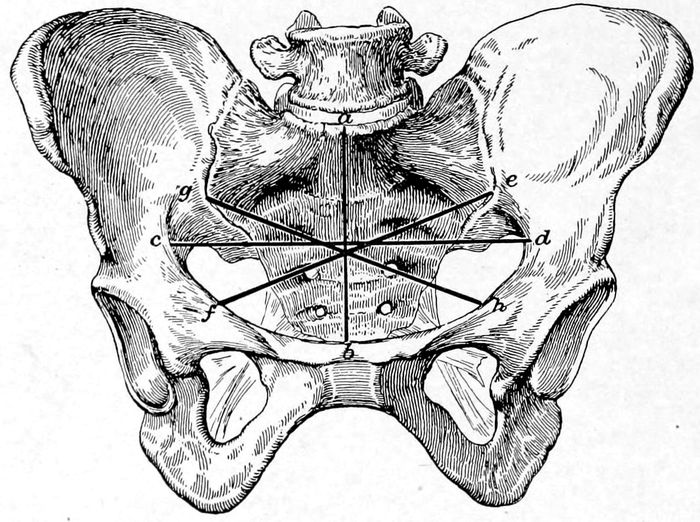

Fig. 1.—The normal female pelvis. (Eden.) The lines ab and cd divide the pelvis into the right and left anterior and the right and left posterior quadrants. ab indicates the anteroposterior diameter of the brim, cd shows the transverse diameter while gh and ef represent, respectively, the right and left oblique diameters.

19The brim or inlet has four important diameters to be

remembered; important because the hard, round head

of the child must pass through them by accommodating

its diameters as favorably as possible to those of this

opening. These diameters are named respectively the

anteroposterior or conjugate diameter, the transverse,

and the right and left oblique diameters. The two

oblique diameters attain their greatest importance when

the pelvis is irregularly distorted, but the others are

essential in every case where labor impends. It is to

secure an estimate of these latter diameters that the

bony prominences are measured. This upper opening

lies not horizontally, but in oblique relation to the body

in standing position, and the weight of the abdominal

viscera rests largely upon the bones and in consequence

does not crowd into the inlet unless forced in by corsets

or faulty habits.